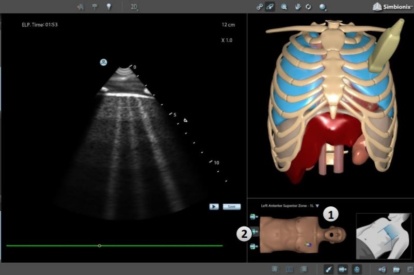

Ultrasound Mentor accelerates the development of basic to advanced technical and cognitive skills, by providing not only the probe manipulation training, but also a didactic environment enabling structured, self-guided learning including step-by-step instructions and educational aids such as 3D anatomical map and probe positioning assistant, all backed up with our progress monitoring tool MentorLearn.

- Step-by-step tasks provide a self-learning opportunity for sonography skills and scanning protocols

- Advanced diagnostic tools, including Color Doppler, CW, PW, M-mode, and measurements

Bedside Echocardiography Module

Advanced Echo Module